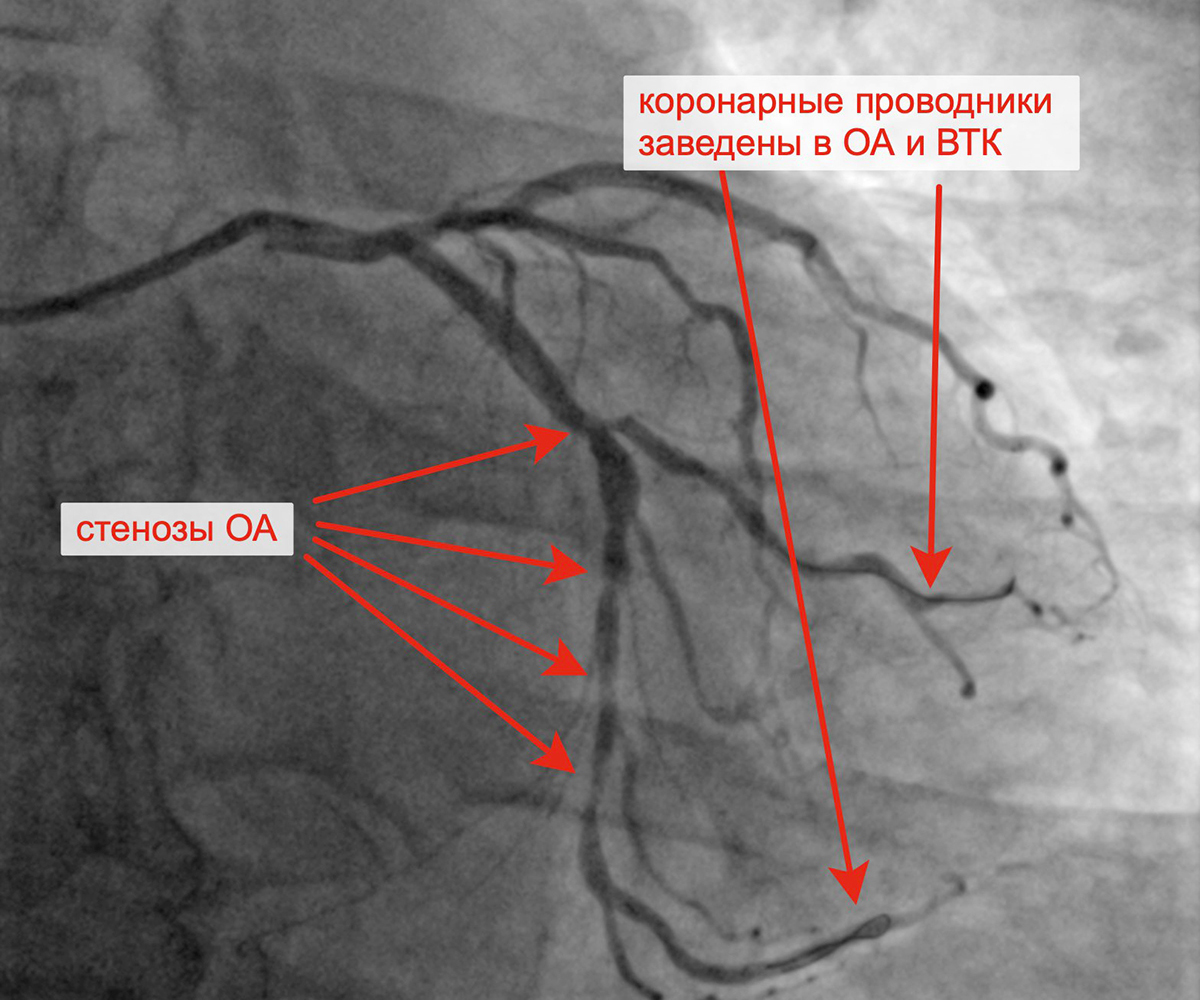

В марте 2023 г. в связи сохраняющейся одышкой, загрудинными болями при физической нагрузке пациент госпитализирован в кардиологическое отделение для решения вопроса о проведении следующего, третьего этапа реваскуляризации. Учитывая наличие ангинозных болей, результаты проведенных обследований (положительным стрессЭХО), коронарографии, наличие гемодинамически значимых стенозов коронарных артерий, принято решение о проведении баллонной ангиопластики и стентирования огибающей артерии (2 стента с лекарственным покрытием). Контрольная ангиография после успешного чрескожного коронарного вмешательства: стенты и ОА с ветвями проходимы, позиционирование стентов адекватное, диссекции или остаточного стеноза в стентированном сегменте ОА нет, кровоток TIMI 3 по ОА и всем ветвям.

Критические стенозы ОА Заведены проводники в ОА и ВТК

Имплантация первого стента в ОА Имплантация второго стента в ОА

Финальный результат имплантации 2 стентов в ОА